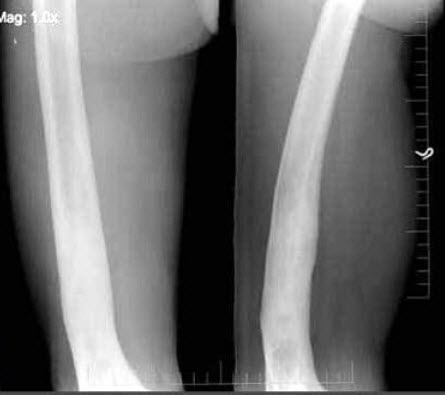

59、单项选择题

女,12岁,左前臂外翻畸形4年,摄片如图所示,最可能的诊断是()

A.奥利氏病

B.马德隆氏畸形

C.先天性干骺端发育不全

D.软骨发育不全

E.以上均不正确

71、单项选择题

女,12岁,右小腿肿胀,疼痛,发热3月余,摄片如图所示,下列征象哪项是错误的()

A.骨质呈溶骨性破坏

B.骨质增生硬化

C.骨膜呈层状增生不明显

D.可见软组织肿块

E.软组织肿胀